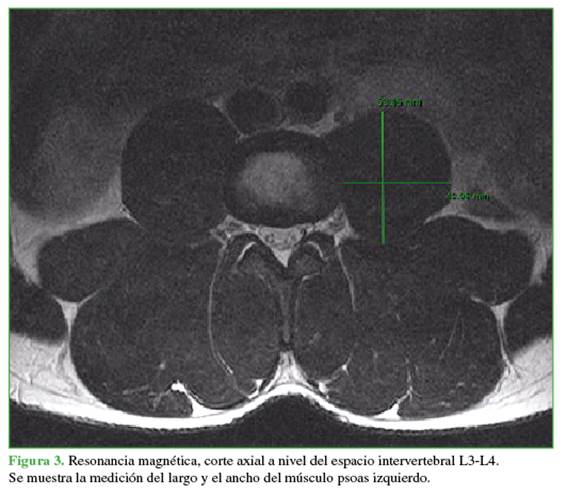

Se utilizó el método Moro17 que divide el espacio intervertebral en seis zonas que van de anterior a posterior (Figuras 1 y 2). El aspecto anterior del margen anterior del cuerpo vertebral fue definido como zona A; el aspecto posterior del margen posterior, como zona P; las zonas I, II, III, IV fueron distribuidas igualmente entre el margen anterior y el margen posterior, del anterior al posterior. La distribución de los grandes vasos abdominales en cada zona de cada espacio intervertebral lumbar fue analizada sobre la base de las imágenes de RM; el ancho del psoas en cada zona de cada espacio intervertebral lumbar de ambos lados se midió con el programa del análisis de imagen (PACS Carestream©). El espesor del psoas se definió como la distancia entre los puntos medios de los márgenes interior y exterior del psoas mayor en cada zona (Figura 3).

Distribución del psoas mayor izquierdo

Se evaluó el grosor del músculo psoas izquierdo en cada nivel y en las zonas I, II, III y IV. En el nivel L1-L2 de la zona I, las mujeres presentaron una media de 0,41 mm; 4,12 mm para la zona II; 7,32 mm para la zona III y 10,51 mm para la zona IV. En L2-L3, se observó una media de 2,67 mm para la zona I; 10,56 mm para la zona II; 14,08 mm para la zona III y 16,76 mm para la zona IV. En L3-L4, la media fue de 8,80 mm para la zona I; 18,78 mm para la zona II; 22,33 mm para la zona III y 24,06 mm para la zona IV. Por último, en L4-L5, la media fue de 23,89 mm para la zona I; 30,26 mm para la zona II; 30,83 mm para la zona III y 24,49 mm para la zona IV (Tabla 3).

En el nivel L1-L2 de la zona I, los hombres presentaron una media de 1,87 mm; 8,31 mm para la zona II; 12,18 mm para la zona III y 15,92 mm para la zona IV. En L2-L3, se observó una media de 9,57 mm para la zona I; 18,68 mm para la zona II; 21,68 mm para la zona III y 24,38 mm para la zona IV. En L3-L4, se observó una media de 22,62 mm para la zona I; 30,56 mm para la zona II; 32,26 mm para la zona III y 30,77 mm para la zona IV. Por último, en L4-L5, la media fue de 39,24 mm para la zona I; 40,94 mm para la zona II; 36,59 mm para la zona III y 25,65 mm para la zona IV (Tabla 4).